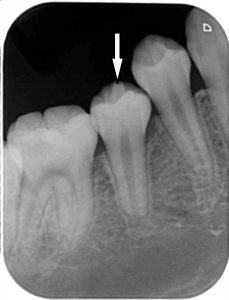

レントゲンにおいても、突起の中央の先端まで、神経の黒いスジがはいりこんでいます。

厄介なことに、突起の先端まで神経が入り込んでいることが多いです。

レントゲン画像で根尖性歯周炎の病巣、黒い影が見られます。